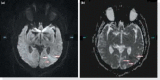

Spinal cord injuries are amongst the most dangerous injuries, leading to high mortality and morbidity. Injured patients are occasionally faced with life-threatening complications and quality-of-life changing neurological deficits. Thoracic and cervical spinal segments are the most effected sites of injury and a wide range of complications including paraplegia, respiratory and cardiovascular compromise secondary to autonomic dysfunction or tetraplegia may ensue. We aim to draw attention to the progressive nature of the neurological deficits in a patient admitted asymptomatically. Also, we would like to discuss the importance of swift diagnosis and management in such patients. In asymptomatic patients in whom no fractures are diagnosed with CT scans, a neurological examination should be repeated several times to exclude any neurological injuries that were missed. MRI should be ordered in an emergency setting even though it is not frequently used as a diagnostic modality. This should be done especially in patients without any fractures on CT but with neurological signs.